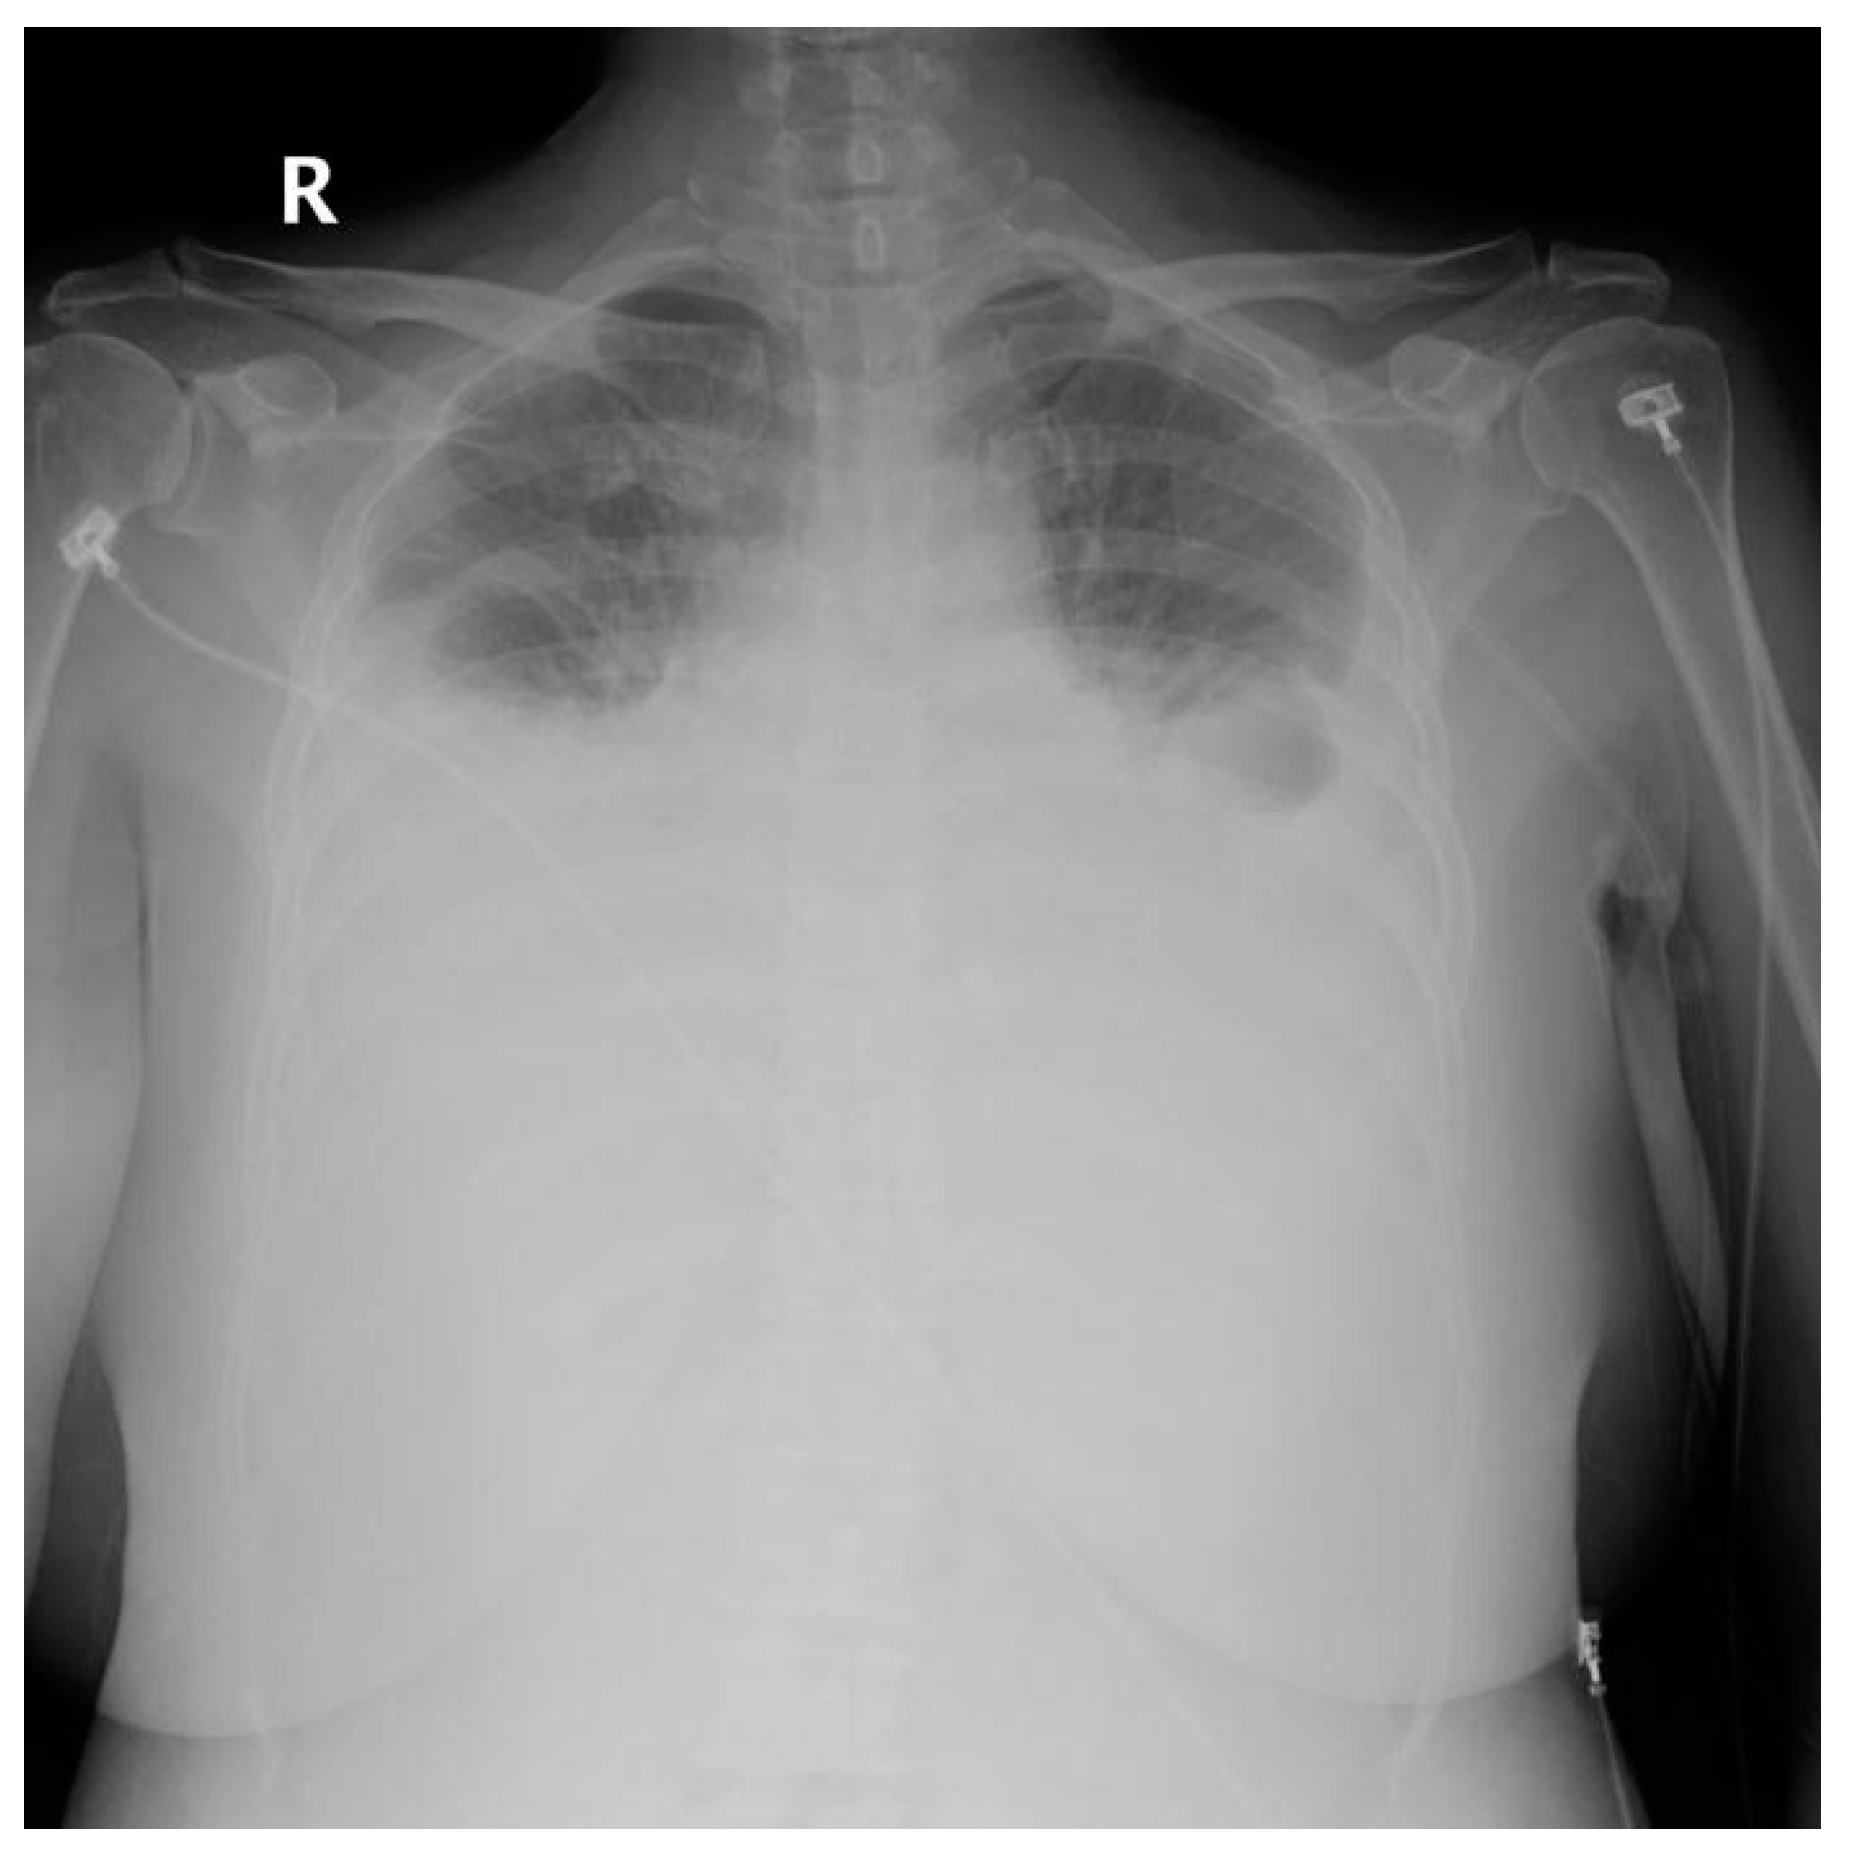

| Site of Pleural effusion | <0.001 | |||

| Right | 1 (1.1%) | 2 (10.5%) | 0 (0.0%) | |

| Left | 0 (0.0%) | 13 (68.4%) | 3 (75.0%) | |

| Both | 0 (0.0%) | 2 (10.5%) | 1 (25.0%) | |

| None | 87 (98.9%) | 2 (10.5%) | 0 (0.0%) | |